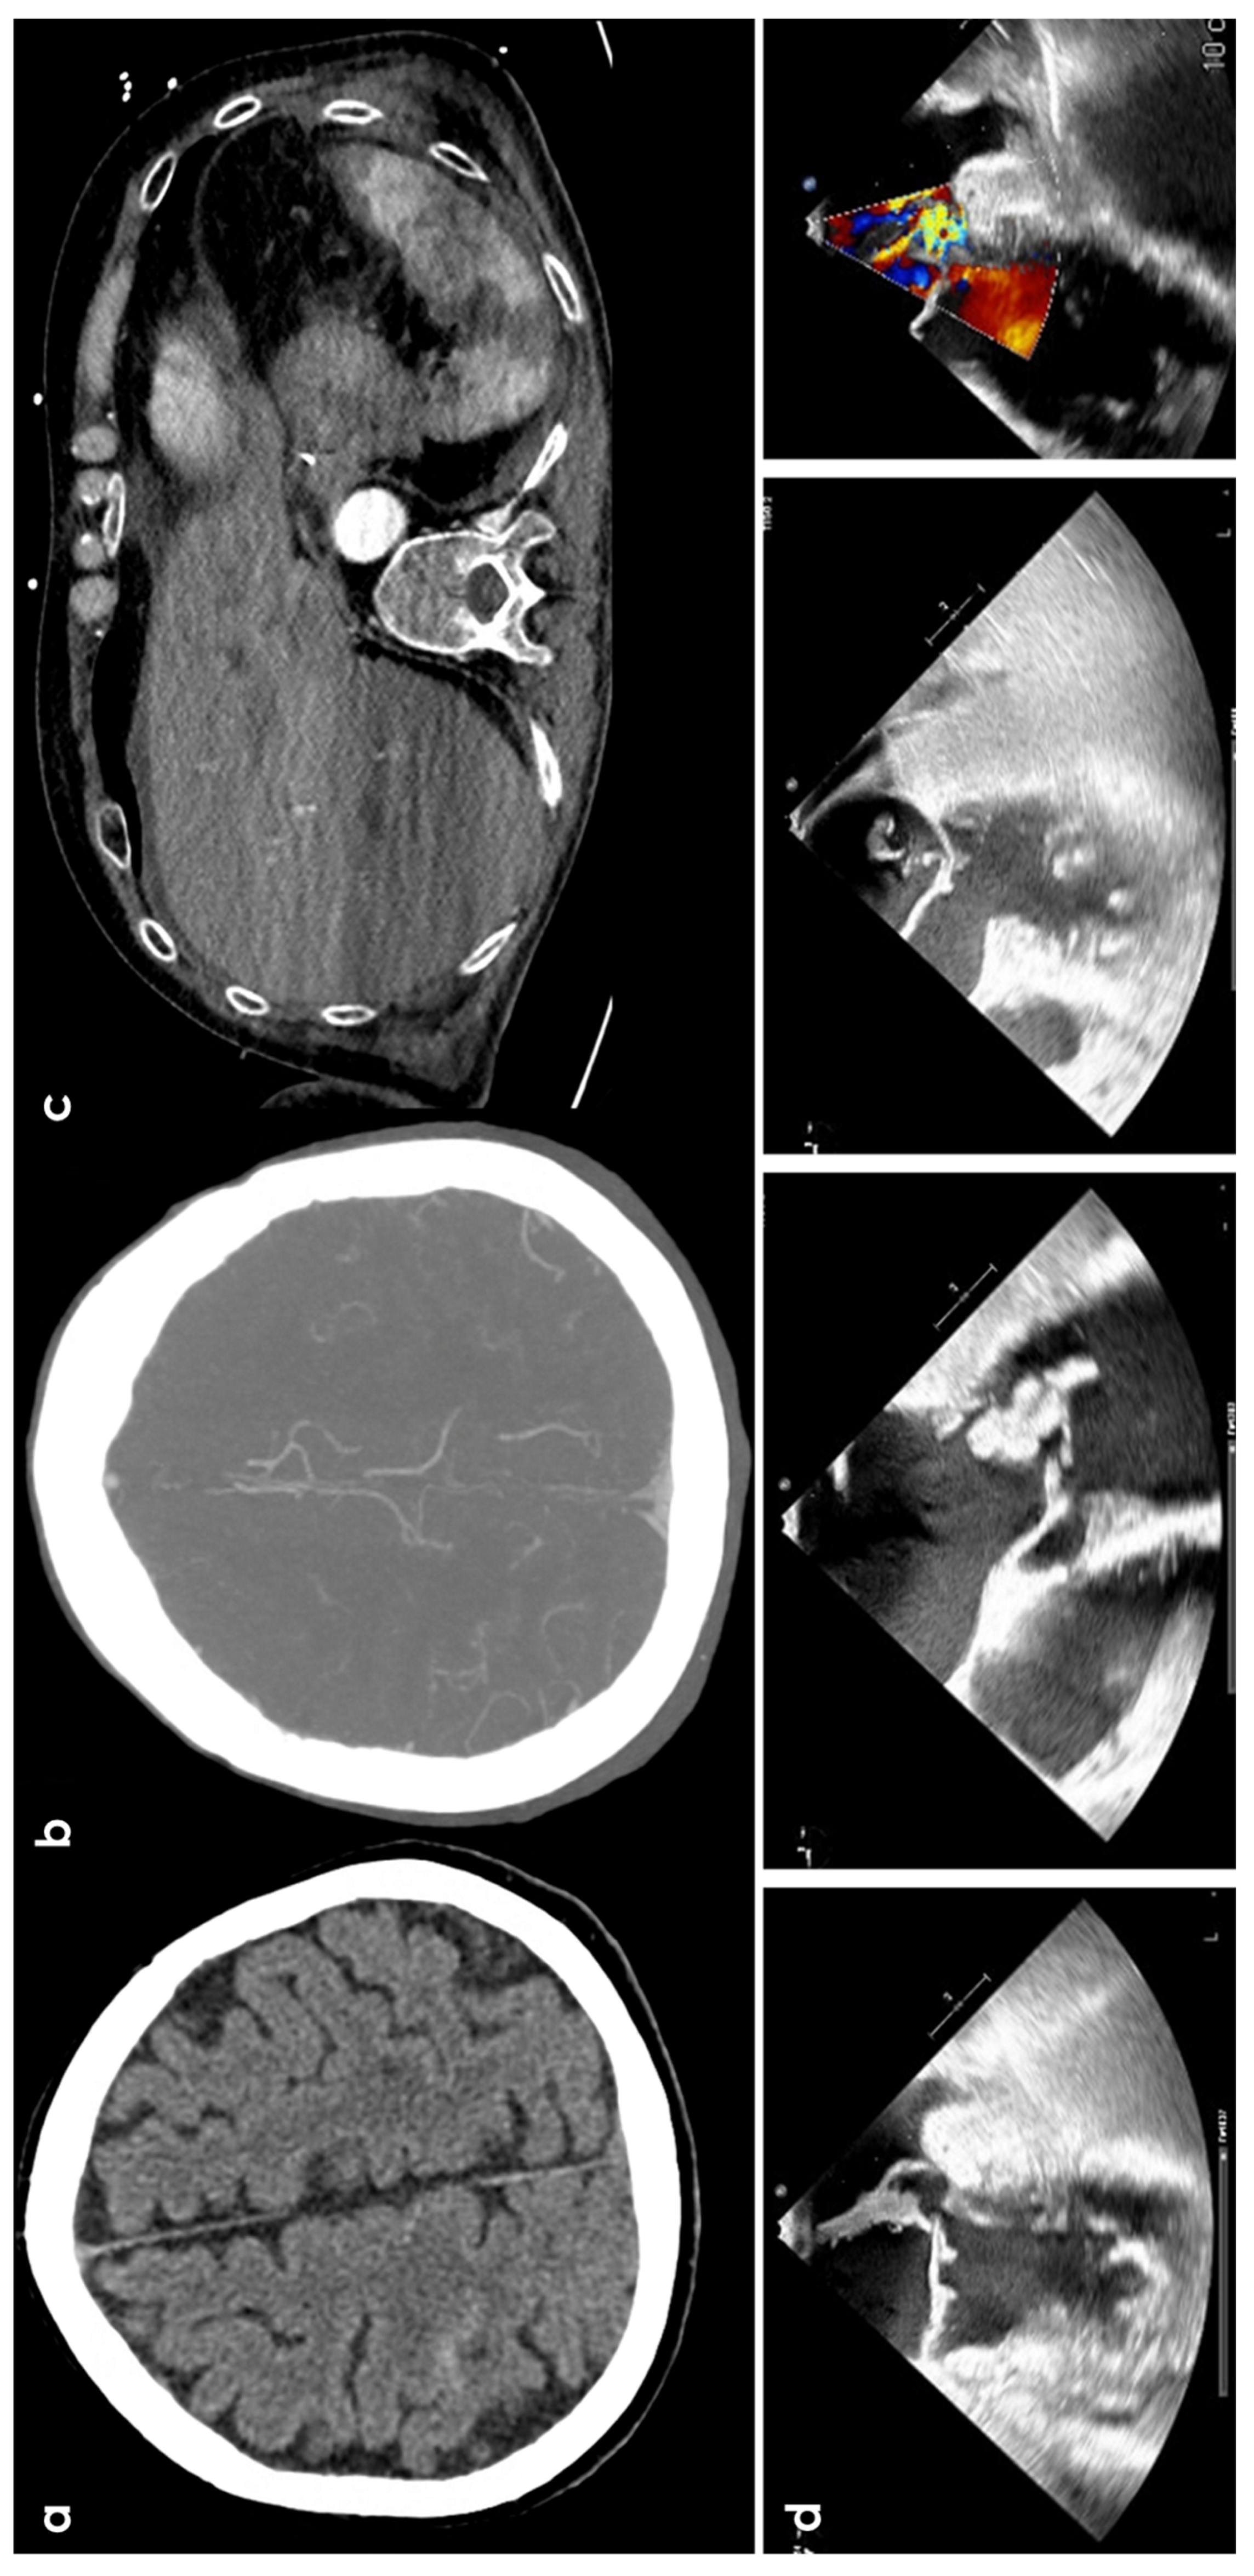

3.3. Infective Endocarditis

3.4. Cerebral Venous Thrombosis